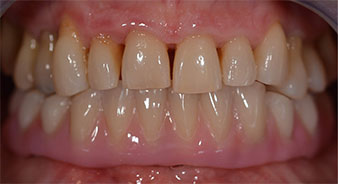

Following the time required for the osseointegration, the final impression of the implants could be performed and the final denture produced accordingly (Fig. 19 and 20). At this point, the dentist and patient were able to decide together whether to use a ceramic or acrylic veneer and a zirconium or metal framework. In this case, Dr. Pascu’s team decided on an acrylic veneer based on the unclear prognosis for the maxillary dentition and the fact that tooth 24 is elongated. This type of veneer is generally considerably easier to adapt and can thus be subsequently altered to reflect the new situation in the maxilla.